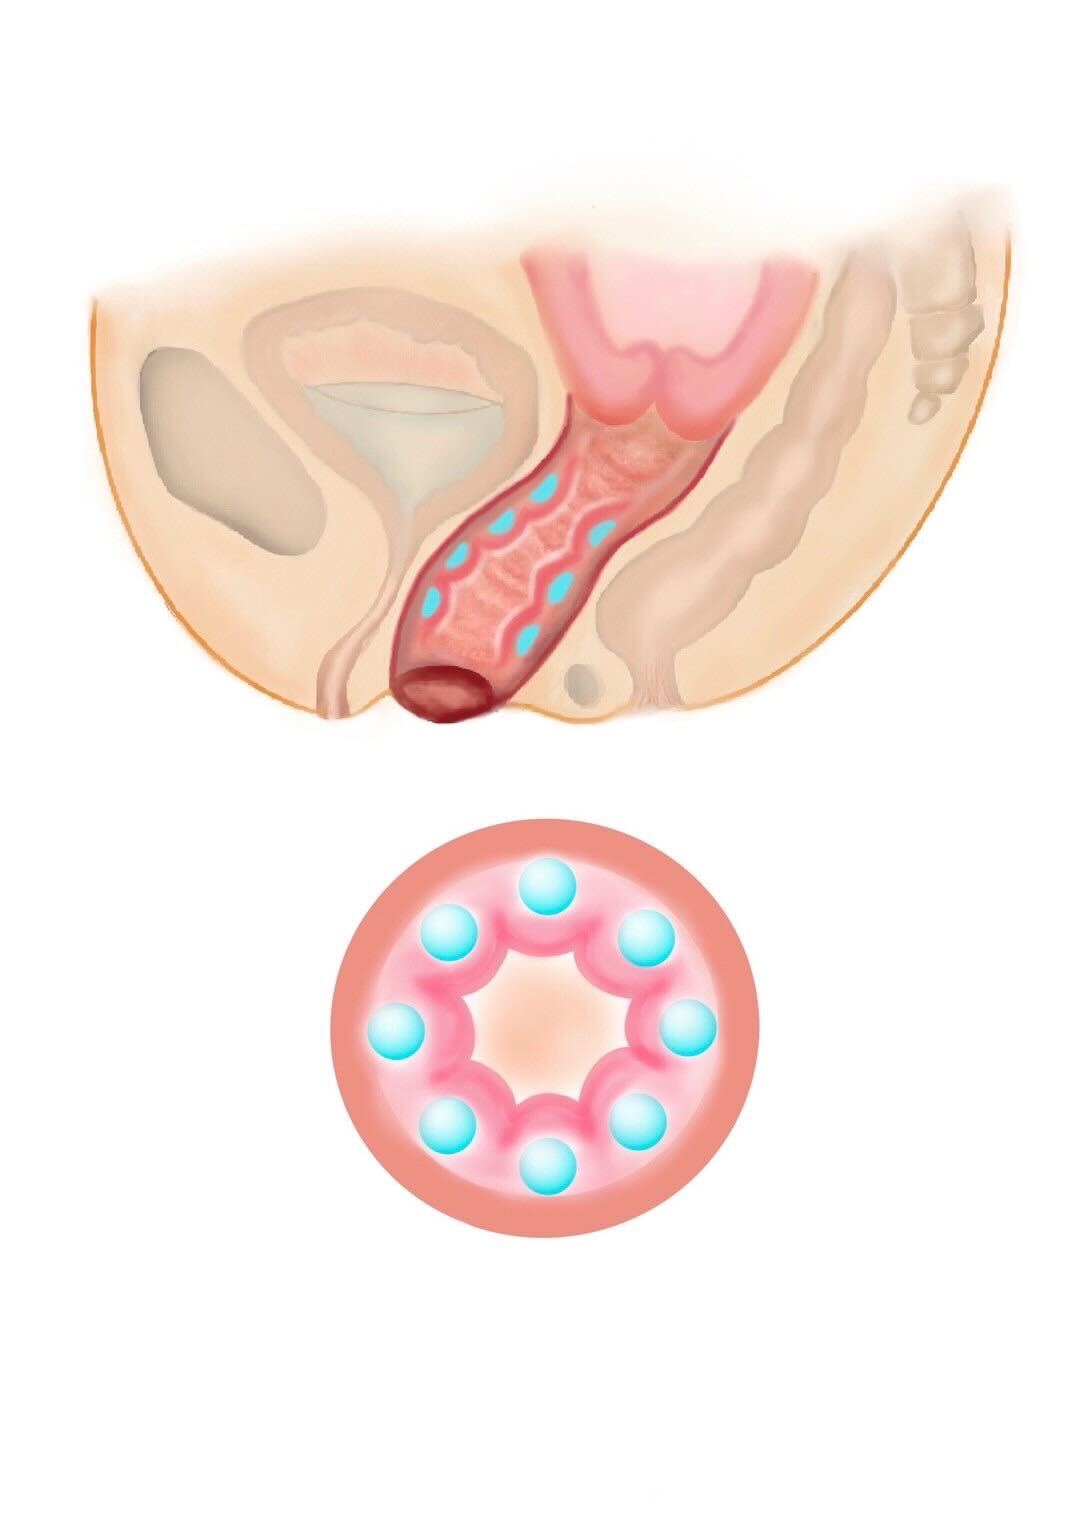

他にもヒアルロン酸注入や再生治療、レーザーなどの治療もありますが、腟壁縮小手術、腟括約筋縫縮術はあらゆる治療の中で最も効果の高い治療になります。腟壁縮小手術では、産後に緩んでしまった腟壁を腟の奥から切開し縮小します。腟周辺の筋肉を縮小縫合し、新たに腟のヒダを形成することが可能です。

また同時に入り口付近にある腟括約筋を縫縮すると、入り口から腟の奥まで縮小され、高い効果が得られます。 腟は直腸に接するようにすぐ前に位置しますので、繊細な作業を要し、高い技術が必要です。

加齢や出産が原因で低下した膣圧を改善する治療です。ヒアルロン酸を注入する部位や量を変えることで、膣内の好きな部位を狭くし自由に膣圧を高めることが可能です。治療直後より効果が実感できます。性行為時の満足度を高めたり、女性として自信が持てたり、尿漏れを改善するなどの効果があります。当院では、膣治療を専門的に行なっているため、お悩みに合わせたカスタム注入が可能です。 ヒアルロン酸は少しずつ体内に吸収され、1.2年でなくなりますので、効果を持続させたい方は追加の注入が必要になります。 効果を持続させたい方は膣内の脂肪注入をご検討ください。 みみず千匹、たこつぼ、きんちゃく、かずのこ天井など、ご希望を伺うことが可能です。

膣内に上下にヒアルロン酸を注入し、パートナー共に性行為時の感度を高めることが可能です。